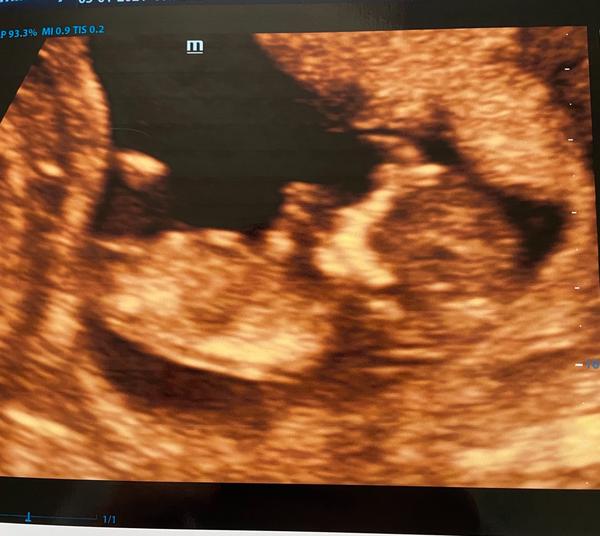

@littlebee11 ahojky, tak mě prcek hezky vyrostl vapadá dokonce na 10+4, takže dobrý a screening mám teda až za 14 dní, dneska byl jen odběr, už jsem zapomněla jak to chodí 😁😉

Holky, sreening dopadl dobře, ale mám neskutečně moc vysoké protilátky. Vystavena žádanka na genetiku a jsem odeslána do rizikové poradny do porodnice. Další utrazvuk za 14 dní. Jinak bylo úžasné vidět, jak se miminko hýbalo a dělalo kotrmalce. Jen mám strach... u mladšího syna po porodu hned měnili krev... teď hrozí, že mu jí už můžou měnit v těhotenství... každopádně miminko nedonosim do termínu.